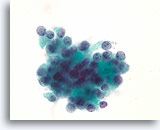

Afbeelding 19

Cellaesie, folliculair neoplasma (lymfocytische thyroïditis vs hurthlecelneoplasma) kan niet worden uitgesloten, schildklier FNA, ThinPrep®.

De hurthlecellen hebben een microfolliculaire organisatie. Er zijn een paar lymfocyten door het epitheel gemengd, hetgeen pleit voor lymfocytische thyroïditis.

60X

Afbeelding 19

Cellaesie, folliculair neoplasma (lymfocytische thyroïditis vs hurthlecelneoplasma) kan niet worden uitgesloten, schildklier FNA, ThinPrep®.

De hurthlecellen hebben een microfolliculaire organisatie. Er zijn een paar lymfocyten door het epitheel gemengd, hetgeen pleit voor lymfocytische thyroïditis.

60X